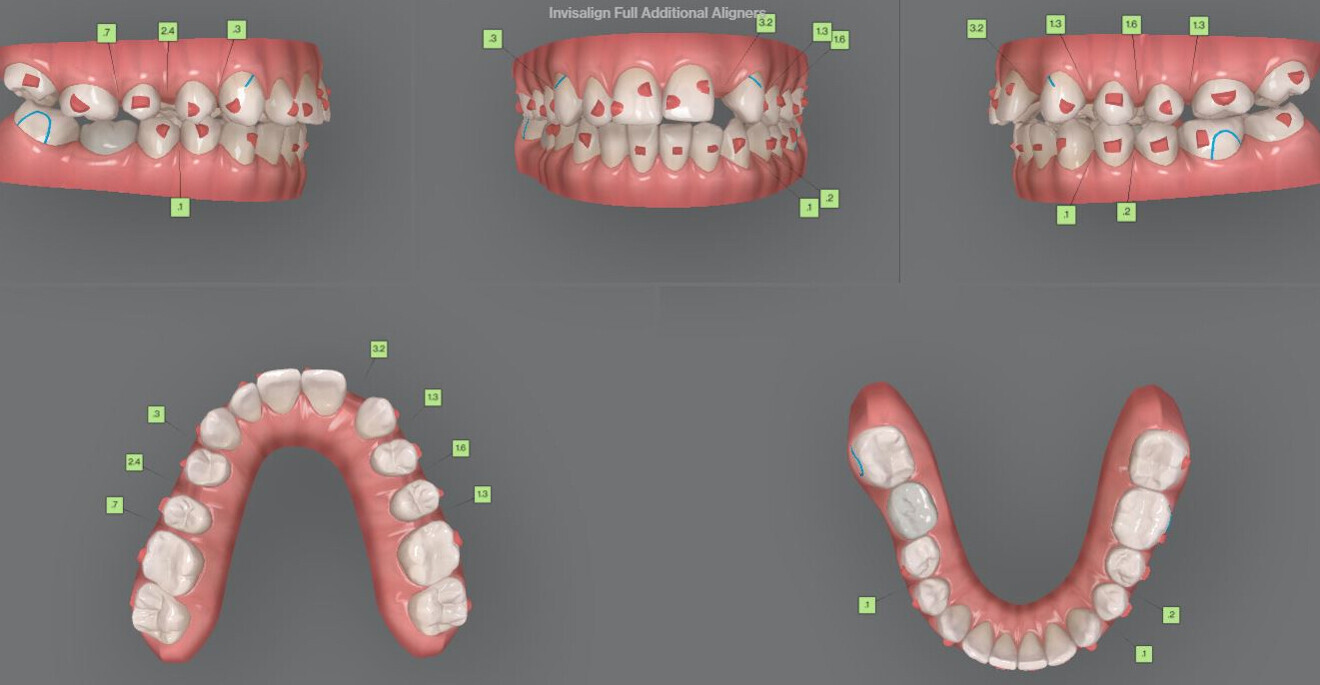

Fig. 2: Pretreatment digital models.

Fig. 8: Additional aligners ordered.